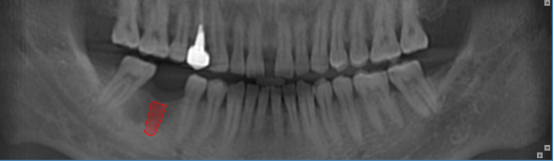

正畸通过扫描形成图像,包括曲面体层、头颅侧位进行测量图像。2D和3D图像在确定多生牙的存在及位置方面,有着巨大的差别。3D图像对扫描区域有着完整,综合的展示,甚至允许通过不同视角,以及对不同断面重建图像进行观察。